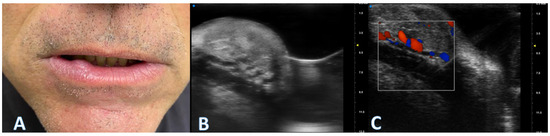

Reliability of Ultrasonographic Assessment of Depth of Invasion and Tumor Thickness in Intraoral Mucosa Lesions: A Preliminary Experience

2.2. UHFUS Scan Protocol